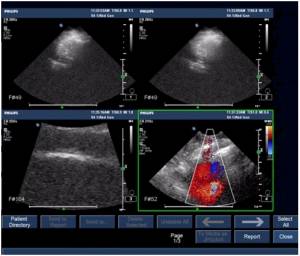

按下iU/iE机器键盘上面的“Review”按键,打开病人数据库的浏览界面,我们先来认识一下这个界面:

中间区域,显示的就是病人资料了。在这里有个特别重要的标识需要给您介绍一下,您可以看到每个病人资料的前面有个选择框:

方法也非常简单。在病人目录区用轨迹球左键双击条目,就到了单个病人资料窗口: